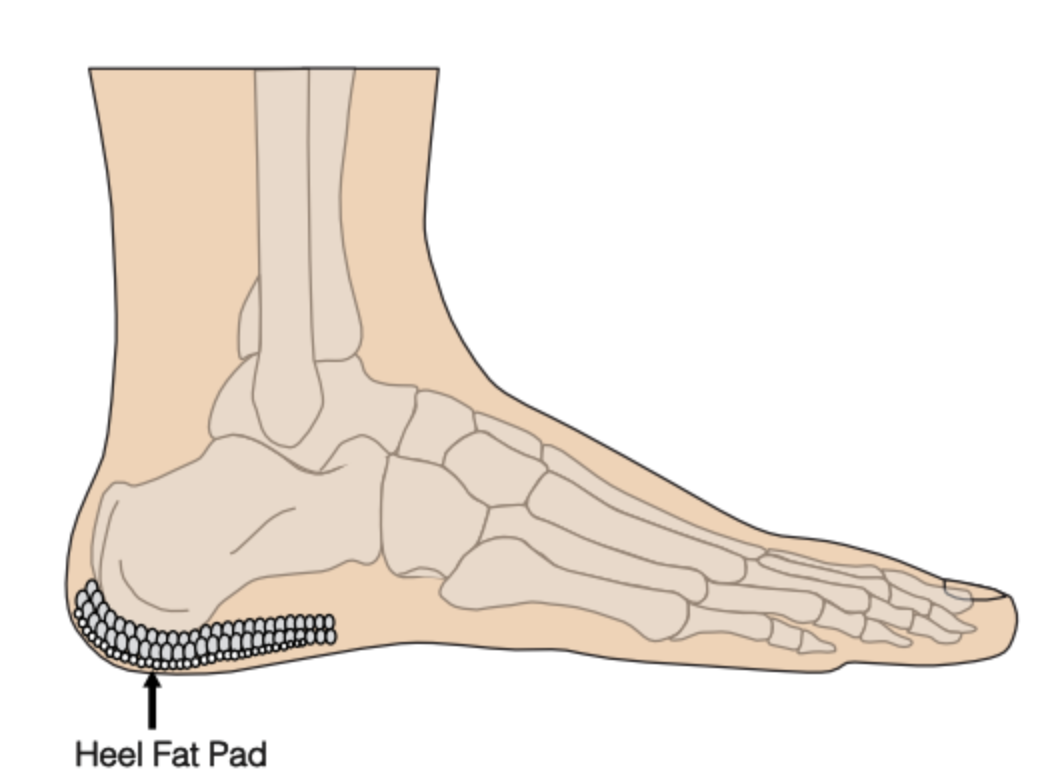

What is meant by fat pad atrophy? [1]

Thinning and degeneration of the fat pad of the heel (soft tissue layer in between the skin and the heel bone)

This makes the heel bone more vulnerable to repetitive microtrauma. This can lead to chronic inflammation, bruising, swelling and pain within the heel bone.

How does fat pad atrophy present? [1]

Symptoms are similar to plantar fasciitis, with pain and tenderness over the plantar aspect of the heel. Symptoms are worse with activities, particularly when barefoot on hard surfaces.

The thickness of the fat pad can be measured with an ultrasound scan.